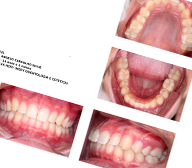

Documentação Ortodontica

Documentação Ortodôntica é um conjunto de exames (radiografias, fotografias intra e extra-bucais) cuja finalidade é proporcionar uma visão abrangente do paciente, permitindo maior detalhamento e entendimento do caso pelo dentista.